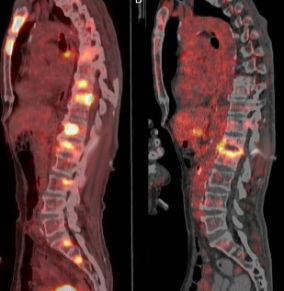

PET (Positron emission tomography)

PET, glikoz metabolik aktiviteyi gösterir. Yalnız kemikte değil vücudun herhangi bir yerindeki aktivite artışınıda gösterir. Aktivite artışı tümöre spesifik olmayıp, travma iyileşmesinde ve enfeksiyonda da görülebilir.